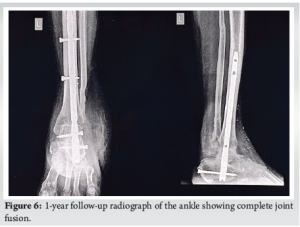

The tibia, talus, and calcaneus were carefully aligned to maximize bone contact and create a plantigrade foot. The hindfoot was positioned at 0° dorsiflexion, 5° heel valgus, and 5–10° external rotation. After debriding both articular surfaces, a guidewire was inserted as shown in (Fig. 4) through the subtalar and tibiotalar joints under arthroscopic guidance. Once the intramedullary reaming was completed, the appropriately sized retrograde nail was inserted, and confirmed under the image intensifier as shown in (Fig. 5). The proximal screw was inserted first followed by a talar screw and at last calcaneo-cuboid screw with compression device was inserted. Following the procedure, the ankle was stabilized in a below-knee plaster cast for a duration of 3 weeks to ensure immobilization and promote soft tissue healing. Graduated partial weight-bearing with bilateral axillary crutches was commenced at the 4-week post-operative mark to progressively restore functional mobility while minimizing stress on the healing structures (Fig. 6).